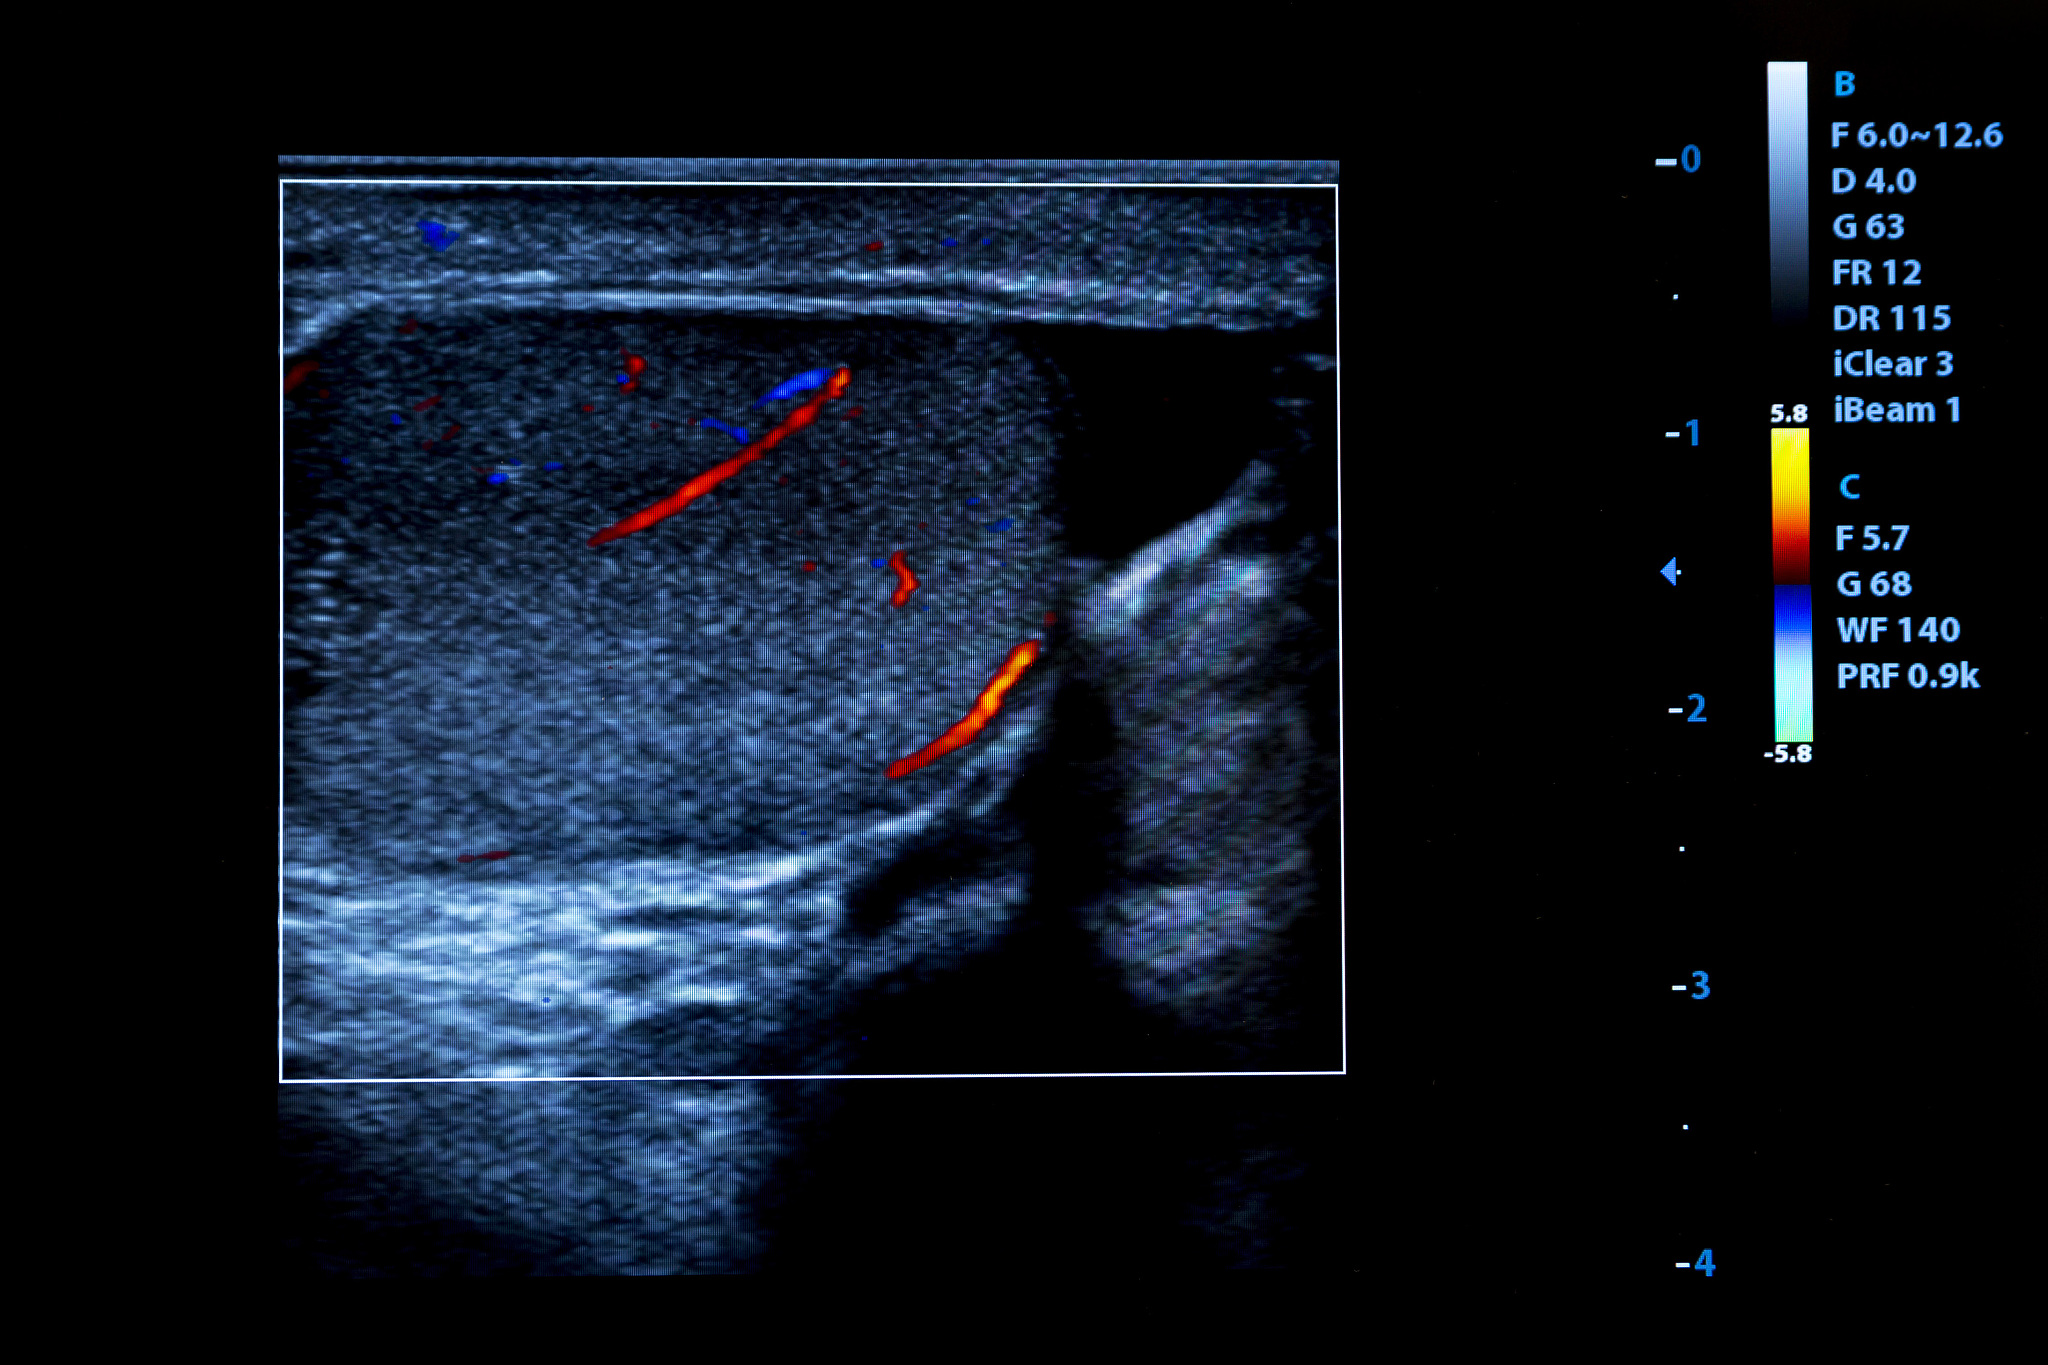

腔内超声造影是一种通过将超声造影剂注入胆道系统来增强超声图像的方法。它可以用于诊断胆道疾病,如胆石症、胆管扩张、胆管狭窄、胆管结石、胆囊炎等。

使用腔内超声造影可以清晰地显示胆管内部的结构和病变,能够帮助医生确定病变的性质和位置,以及评估病变的程度和范围。此外,腔内超声造影还可以用于引导胆道内的治疗操作,如胆管置管、胆管扩张术、胆管置入支架等。

总之,腔内超声造影是一种非常有价值的检查方法,可以帮助医生更准确地诊断和治疗胆道疾病。